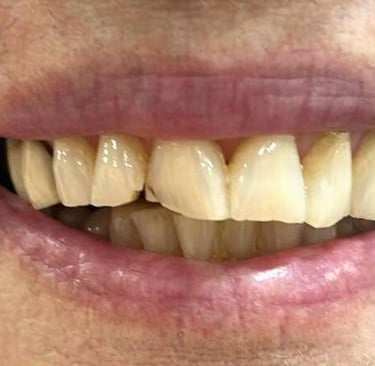

Aspecto Clínico Inicial - Fotografias originais — nenhuma contém retoques

Antes